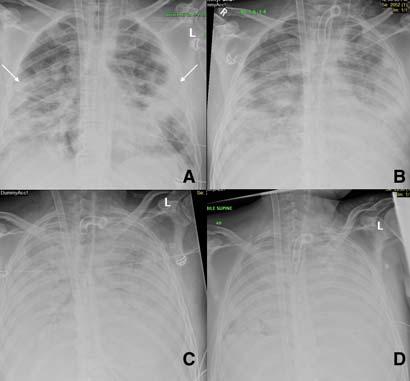

Fig 2 — CXR (A) and CT (B& C) images of a 50-year-old man with 6 days history of fever and dry cough. RT-PCR test was positive. CXR shows bilateral diffuse opacities, with a more opaque patch in the right lower zone (white arrow). The corresponding CT shows the true extent of the disease (black arrows). Images reproduced with permission from Covid-19 Database of the Fleischner Society.

Fig 5 — CXR’s of different patients with proven COVID-19 demonstrating varied appearances at the time of presentation. ANo abnormalities could be seen on CXR and the corresponding CT (not shown) was also near normal. B- Ill-defined hazy peripheral opacities seen in the left upper zone. C- Multifocal opacities were seen in the right lung on CXR at presentation. D- CXR showing extensive parenchymal infiltrates in a patient who came to the hospital in very bad respiratory distress and was found to have COVID-19 on testing.